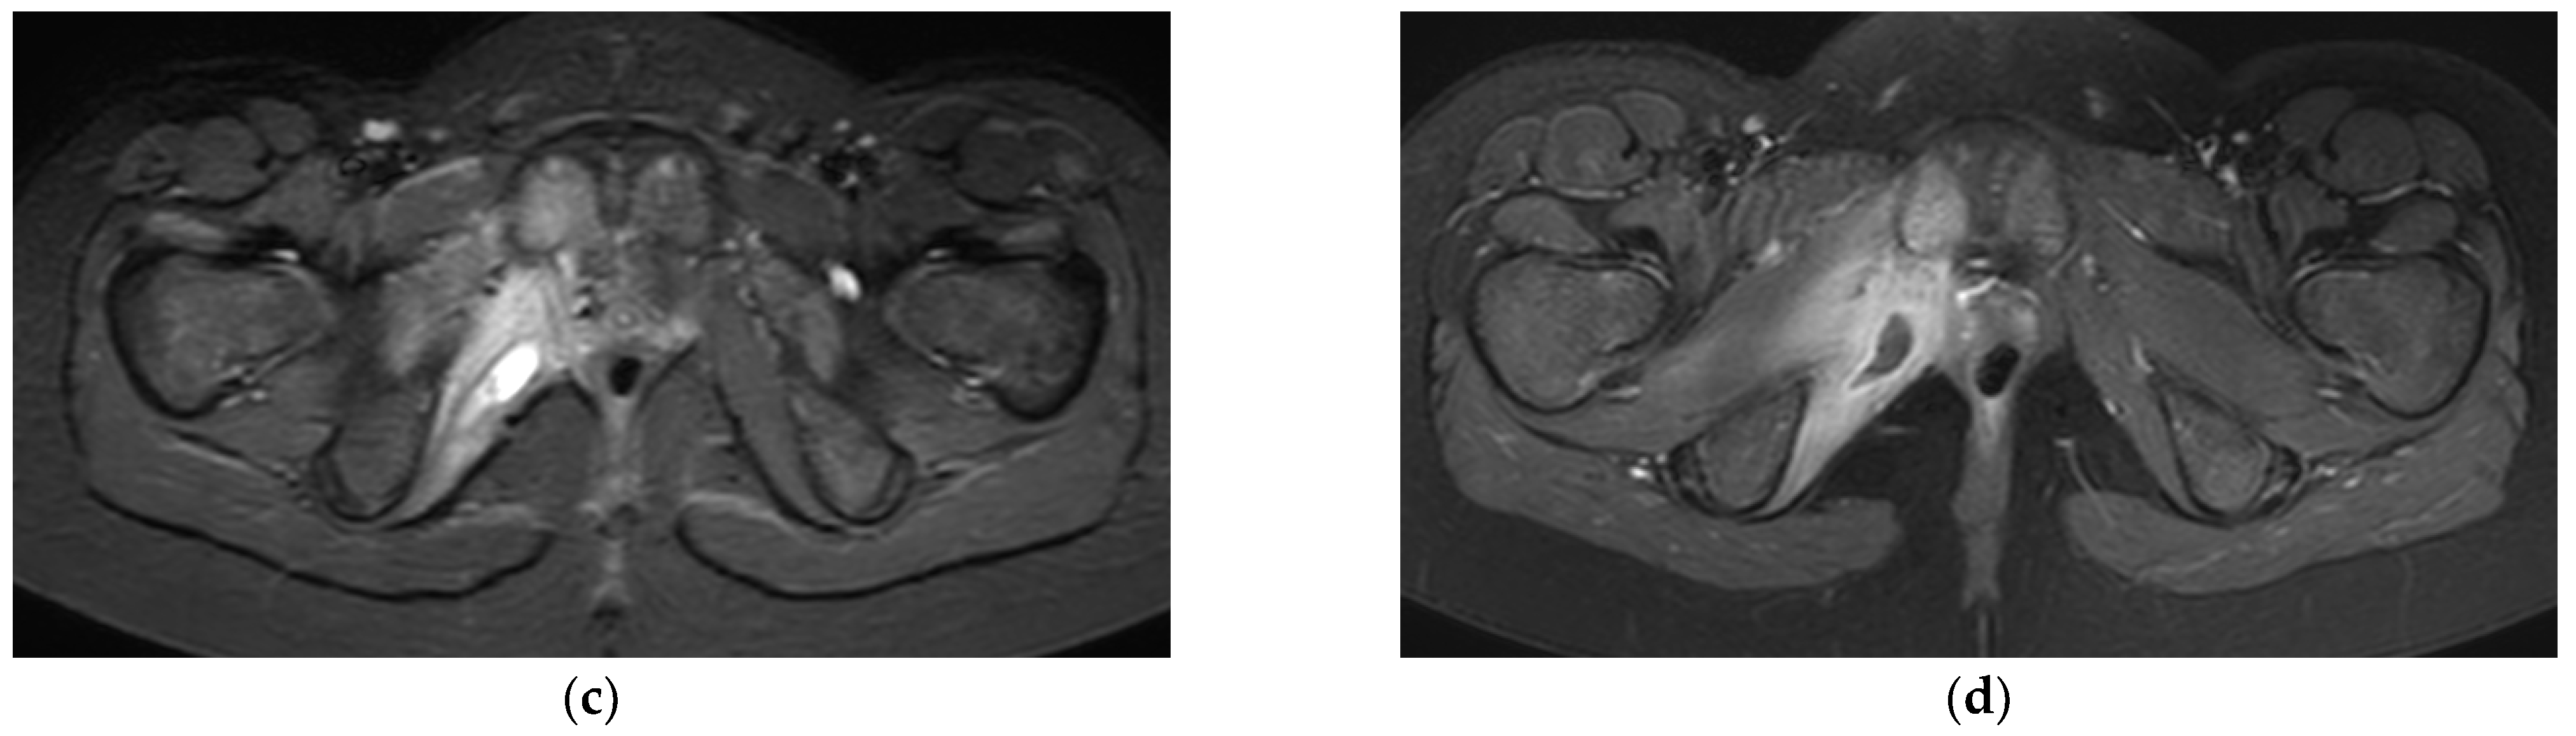

- Trusen, A.; Beissert, M.; Schultz, G.; Chittka, B.; Darge, K. Ultrasound and MRI features of pyomyositis in children. Eur. Radiol. 2003, 13, 1050–1055. [Google Scholar] [CrossRef]